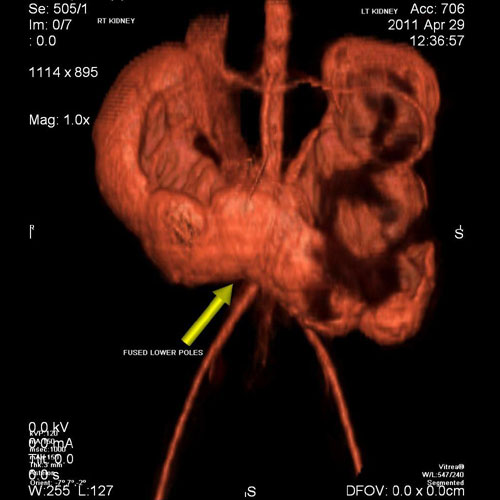

SCAN3

7 year old boy with pain in abdomen on left side. CECT with 3 D reconstruction shows a ‘Horse - Shoe’ shaped kidney with obstructed left side kidney. Horseshoe kidneys are the most common type of renal fusion anomaly. A horseshoe kidney is formed by fusion across the midline of two distinct kidneys. They are connected by an isthmus of either functioning renal parenchyma or fibrous tissue. With a horseshoe kidney, ascent into the abdomen is restricted by the inferior mesenteric artery (IMA) which hooks over the isthmus. Hence horseshoe kidneys are low lying.